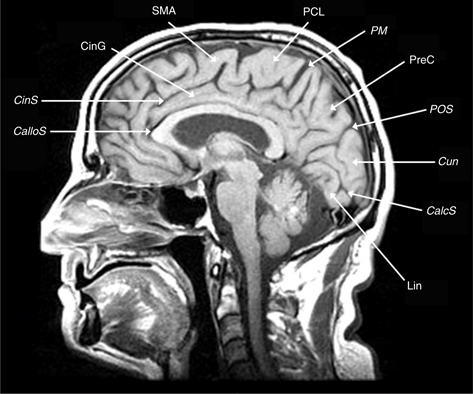

The frontal lobe contains three gyri (superior, middle, inferior) separated by the superior and inferior frontal sulci. The superior frontal gyrus is appreciated on both axial and sagittal images (Figure 1). The middle frontal gyrus (MFG) extends posteriorly and fuses with the vertically oriented precentral gyrus. The precentral sulcus starts at midline and extends anteriorly and laterally in an oblique direction. The next key finding is the merging of the inferior frontal sulcus with the inferior ramus of the precentral sulcus, forming a “T” shape (4, 5). More posteriorly, the central sulcus is identified over the convexity on axial or sagittal images. It is oriented obliquely from posterior to anterior and does not extend all the way into the Sylvian fissure. Inferiorly, the precentral gyrus and postcentral gyrus merge under the central sulcus through a “U”-shaped gyrus (the subcentral gyrus). The post-central gyrus is characteristically narrower than the precentral gyrus (4, 5). Posteriorly, the Sylvian fissure is capped by the SMG, which is the anterior most portion of the inferior parietal lobule. Inferiorly, within the temporal lobe, coursing in parallel with the Sylvian fissure, is the superior temporal sulcus, which is capped posteriorly by the angular gyrus, the posterior limit of the inferior parietal lobule. The angular gyrus (Brodmann’s area 39) and posterior aspect of the superior temporal gyrus (STG) (Brodmann’s area 22) represent the primary receptive speech area (Wernicke’s area). The SMG (Brodmann’s area 40) contains fibers from the arcuate fasciculus that connect Wernicke’s and Broca’s areas (4, 5). The cingulate sulcus separates the cingulate gyrus from the medial aspect of the superior frontal gyrus. If followed posteriorly, the cingulate sulcus angles superiorly to form the pars marginalis, marking the posterior aspect of the paracentral lobule. The paracentral lobule houses the central sulcus, Broadman Areas 3,1,2 and 4,6. On axial images, the pars marginalis may be appreciated as a “bracket” (pars bracket) extending symmetrically from midline left and right. Anterior to this are the primary motor cortex and the postcentral sulcus. Areas 3,1,2 relate to the primary sensory cortex, and areas 4,6 include primary motor and supplemental motor areas (4, 5) (Figures 1 and 2).

Figure 2 Midline sagittal T1-weighted MRI scan showing the callosal sulcus (CalloS); cingulate sulcus (CinS); cingulate gyrus (CinG); supplementary motor area (SMA); paracentral lobule (PCL); pars marginalis (PM); precuneus (PreC); parietal-occipital sulcus (POS); cuneus (Cun), calcarine sulcus (CalcS), lingula (Lin).